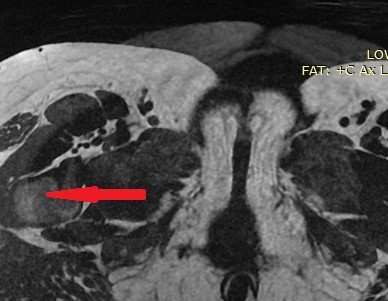

MRI κοιλίας που δείχνει το ευμεγέθες παραγαγγλίωμα στη ρίζα του μεσεντερίου (Ευγενική παραχώρηση Dr. V. Penopoulos)